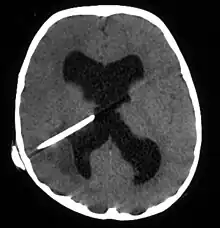

Brain abscess

Brain abscess in a person with a CSF shunt. The abscess is the darker gray region in the lower left of the image (corresponding to the right parietal lobe). The lateral ventricles are visible in black in the center of the brain, adjacent to the abscess.[1]